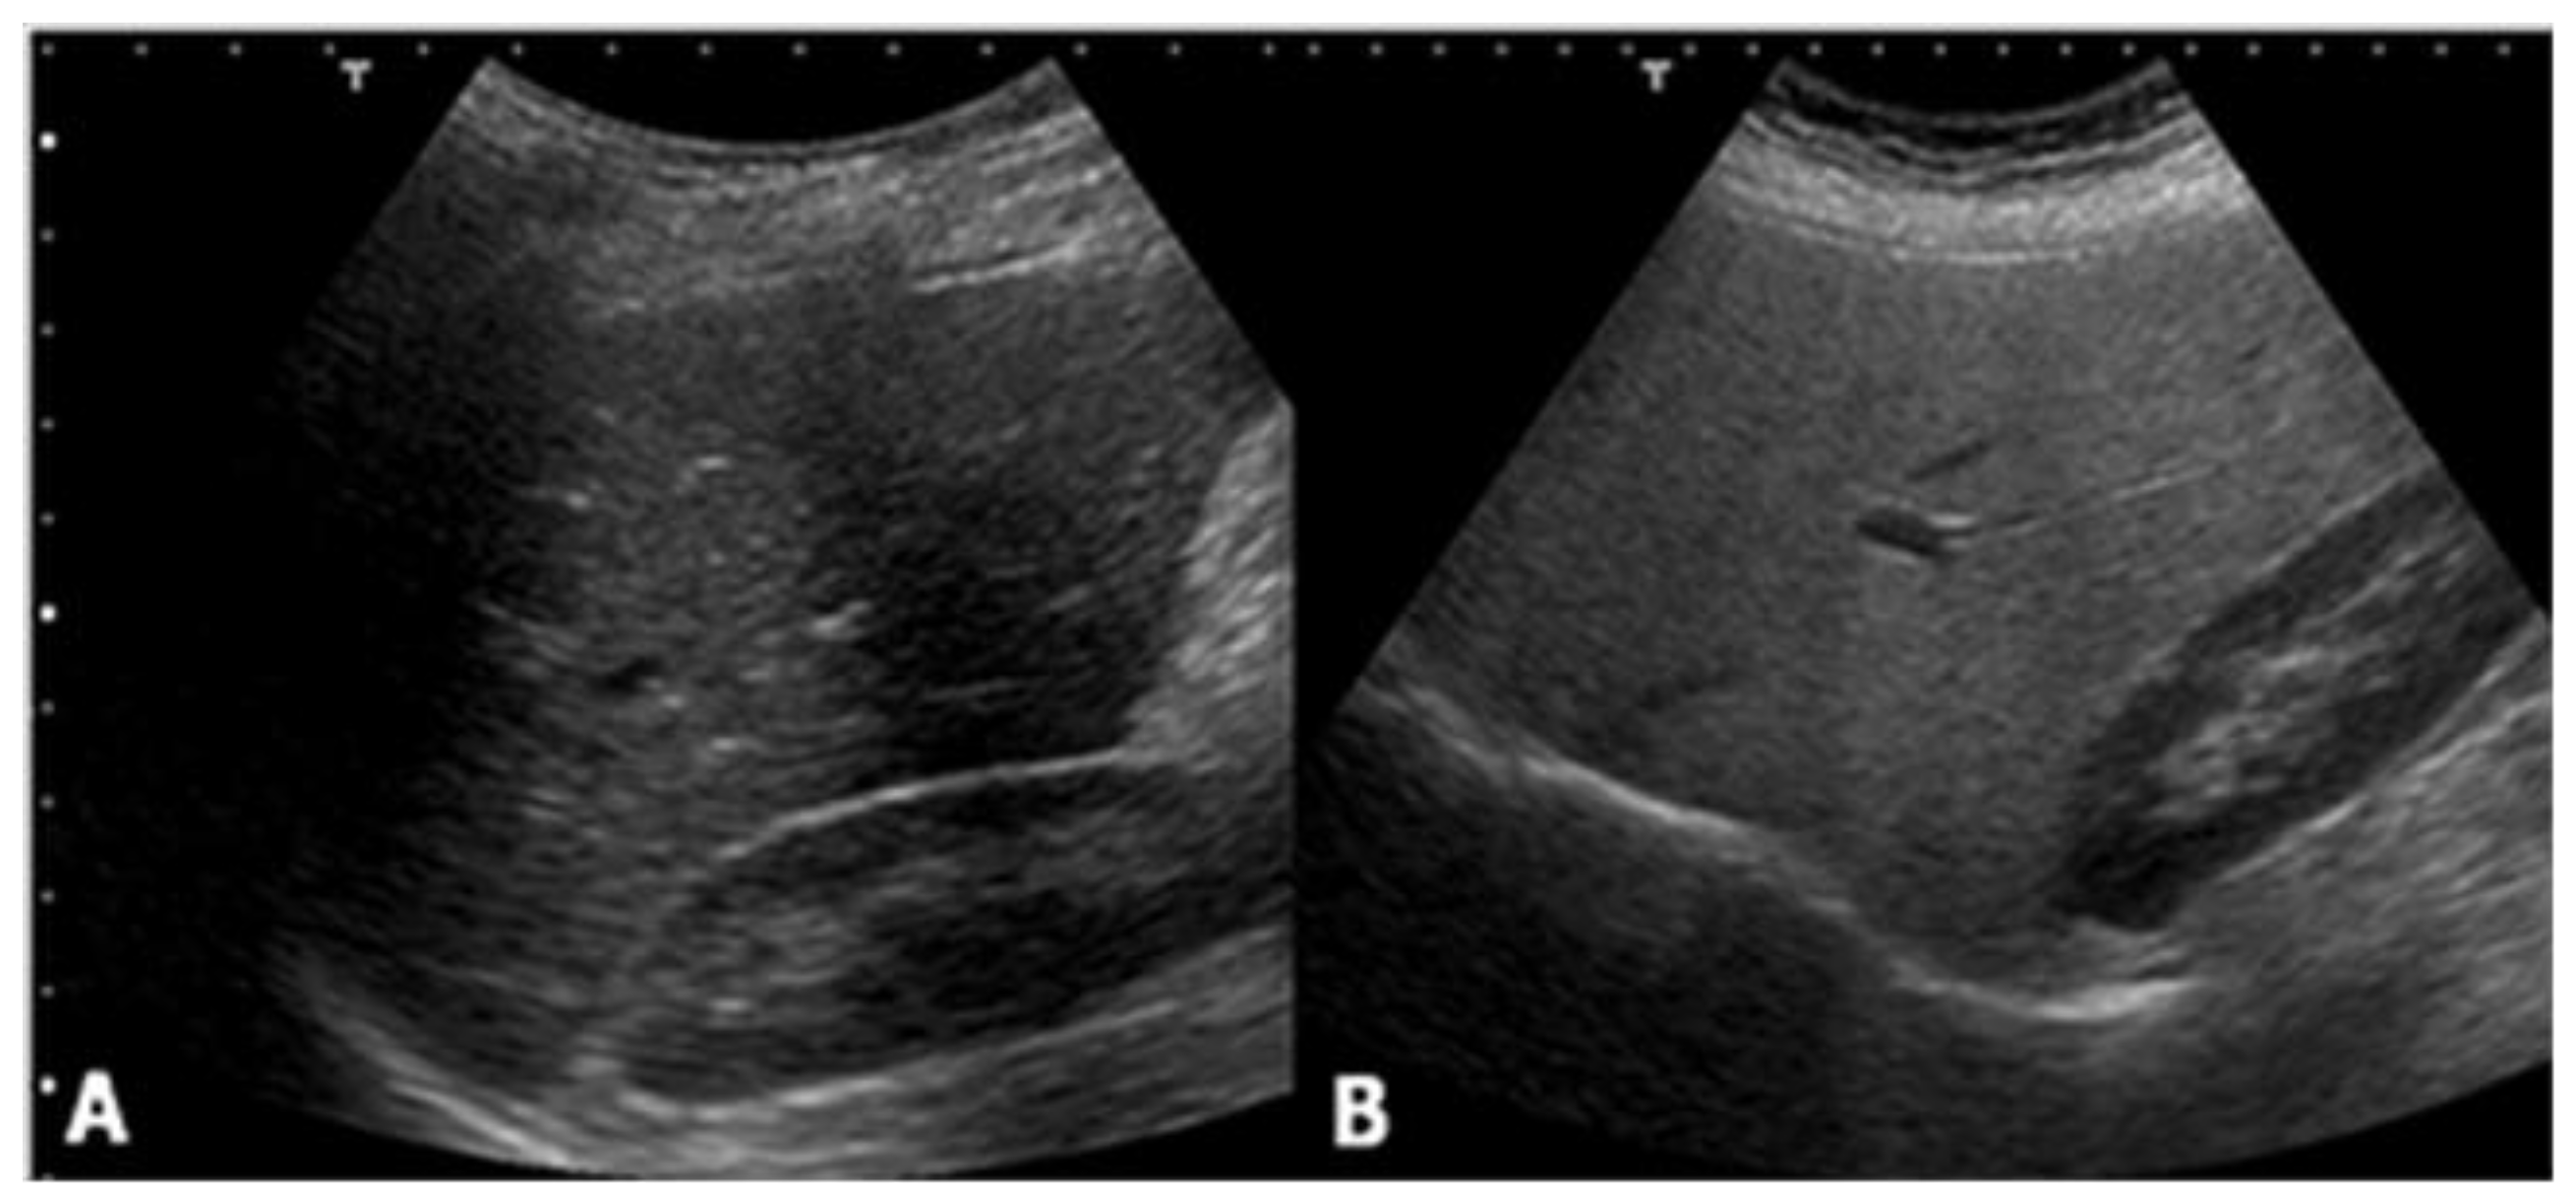

2. Ultrasound

- normal (liver echogenicity similar to kidney);

- mild steatosis (diffuse increase in liver echogenicity);

- moderate (liver echogenicity obscures vessel walls and the diaphragm)

- severe (non-visualization of the hepatic vessels and diaphragm).